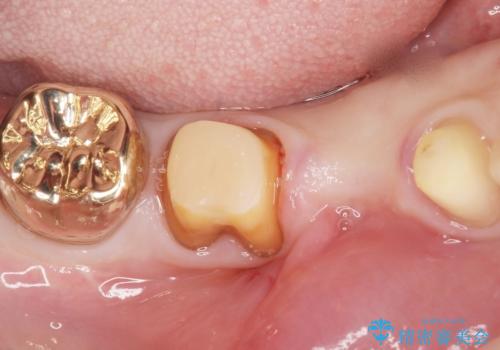

- 右下の奥歯がしみることを主訴に来院された患者様です。

精査したところ、横向きに生えた親知らずのせいで隣の歯(右下7)が虫歯になっていました。

親知らずを抜歯して隣の歯のう蝕を除去し、歯肉の治癒をしっかり待ったのち、患者様のご希望によりゴールド(PGA)クラウンによる補綴を行いました。